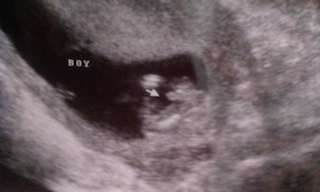

Many pregnant women know their baby's gender (if they choose to know) during their mid-pregnancy ultrasound, usually performed between 16 and 20 weeks. However, if the technician could not get a clear view of the baby's genitals, it may not be possible to say with certainty.

Although the baby's penis or vulva began forming as early as 6 weeks, boys and girls baby looks very similar to the ultrasound until about 14 weeks, and they will be difficult to distinguish them for a few weeks afterwards. By 18 weeks, an ultrasound technician will most likely be able to identify the sex - if the baby is in a position that allows the genitals to be seen. If not, you may be able to tell if you have another ultrasound later in your pregnancy.